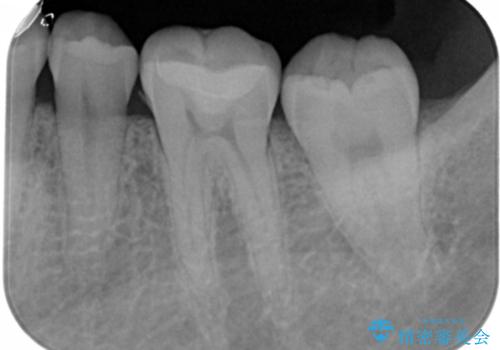

- 左下6番の治療のやり直しを希望し来院された患者様です。

保険の材料が劣化し段差や隙間ができてしまっている状態です。

自費の治療を希望されたため切削量・形態を考慮し、セラミックインレーでの治療を計画しました。

保険の材料と比較して、セラミックは劣化しにくく審美性も高い材料です。